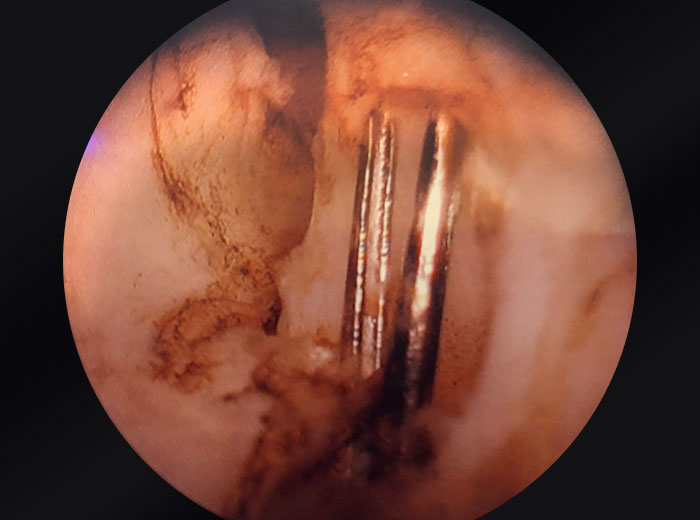

UroLift clips embedded in prostatic tissue

Images provided courtesy of Dr. Ricardo Gonzalez.

OR camera zoomed into prostate.

The steps to doing a trilobar enucleation for doing a PVP VIT procedure remain the same, but the purpose is to work around the clips to be able to excise them in the tissue, whether it’s en bloc, or in fragments that contain that tissue. In my practice, the most reasonable is to do the PVP VIT technique. The GreenLight laser not only cuts through the prostate tissue efficiently, but can cut through the PET portion of the UroLift implant to allow separation of the luminal stainless steel clip, along with the tissue that’s causing obstruction.

And then that procedure’s repeated on the contralateral side. So when the right lobe is treated, you make the incision at the seven o’clock position and 11 o’clock position and remove the tissue in between those two incisions. So the steps are functionally the same. The goal would be to avoid direct laser contact with the metal of the clip, because that may potentially damage the fiber.